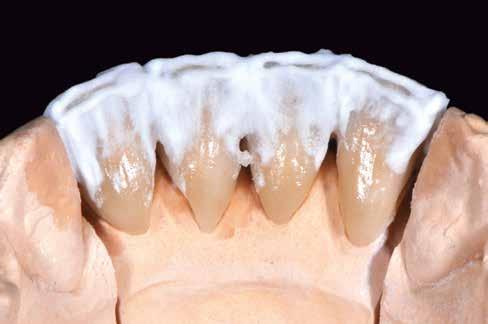

Az előzetes állapotfelmérést és a kezelés megtervezését követően a fogakat minimál invazív módon preparáltuk (1. a-b ábrák), majd az előkészített fogak ínybarázdáiba fonalbehelyező eszköz segítségével (113 Serrated Gingival Cord Packer, Hu-Friedy, Chicago, Illinois) teflonszalagot helyeztünk (Loctite Thread Seal Tape, Henkel Loctite Corp., Egyesült Államok), (1. c ábra). A hagyományos retrakciós fonalak helyett, a rugalmasságuk miatt előnyösebbnek tartjuk a teflonszalagok használatát. A kofferdámot (Dental Dam, Nic Tone, Bukarest, Románia) az előkészített fogakon kívül, az azoktól disztálisan elhelyezkedő egy-egy fognak megfelelően is perforáltuk.

Mivel a felső fogív első kisőrlőfogtól ellenoldali első kisőrlőfogig terjedő részét terveztük kerámia héjak segítségével ellátni (14-24), ezért az izolálást ugyanezen fogív második kisőrlőfogtól második kisőrlőfogig terjedő részére (15-25) helyeztük fel (2. a ábra). A kofferdám rögzítését a második kisőrlőfogakra helyezett kapcsok segítségével (Rubber Dam Clamps #2, Hu-Friedy, Chicago, Illinois, Egyesült Államok) biztosítottuk (2. b ábra). Ezt követően a gumilepedő fogakat körülvevő szélét kézi fonalbehelyező eszközzel és finom levegőáramlattal az ínybarázdákba forgattuk. A folyamat a következőképpen zajlott: a kézi eszközzel a kofferdámot a fognyaknak megfelelően finoman a szulkusz irányába fordítjuk, majd az eszköz végét a fognyaknak megfelelően vezetjük, miközben a lepedőt a puszterből jövő levegő segítsé-

A gumilepedő és a kiválasztott kapcsok (A). A kisőrlőfogakra helyezett kapcsok stabilizálják a kofferdámot (B). A gumilepedő ínybarázdákba történő beforgatása fonalbehelyező eszköz és levegőáramlat segítségével (C). Közvetlenül a héjak felhelyezése előtt a frontfogakra helyezett kapcsok (D).

gével finoman az ínybarázdába fordítjuk (2. c ábra). Azokra a fogakra, amelyekre aktuálisan héjakat akartunk helyezni, ezen felül kiegészítő kapcsokat is helyeztünk (Hygenic Brinker Clamp #B4, Coltene/Whaledent Inc., Cuyahoga Falls, Ohio, Egyesült Államok), (2. d ábra) Ebben a stádiumban érdemes a héjakat még bármilyen ragasztóanyag vagy próbapaszta nélkül a helyükre illeszteni (dry tryin). Erre azért volt szükség, hogy még a tényleges ragasztási folyamat megkezdése előtt ellenőrizni tudjuk a restaurátum és a fog pontos illeszkedését, valamint a széli záródási vonalhoz való akadálytalan hozzáférést (3. a ábra). Ideális esetben a héjak felhelyezését párosával, a középvonaltól disztál felé haladva végezzük. Ennek megfelelően a jobb (1.1) és bal felső nagymetszőfogakra (2.1) kapcsokat helyeztünk, majd a szomszédos fogakat teflonszalag segítségével izoláltuk. Ezt követően az 1.1-es és 2.1-es fogak héjak elhorgonyzására szolgáló felszíneit 32%os foszforsavval (Uni-Etch w/BAC, Bisco Dental, Schaumburg, Illinois, Egyesült Államok) 30 másodpercen keresztül kondicionáltuk. Ez után a felszínek vízzel történő lemosása és óvatosan

leszárítása következett (3. b ábra). A fogfelszínek előkészítésének utolsó lépéseként a primert és az adhezívet (OptiBond FL, Kerr Dental Orange, Kalifornia, Egyesült Államok) a gyártói javaslatnak megfelelően a felszínekre applikáltuk, majd 20 másodpercen keresztül polimerizációs lámpával világítottuk (Valo LED Curing Light, Ultradent Products Inc., South Jordan, Utah). Az 1.1-es és 2.1-es fogakat borító héjak ragasztása során világos színű, fényre kötő ragasztócementet (Variolink Esthetic LC, Ivoclar Vivadent, Schaan, Liechtenstein) alkalmaztunk. A ragasztóanyagot először a héjak belső felszínére vittük fel, majd ezeket az előkészített fogfelszínekre helyeztük (3. c ábra). Az approximális felszíneken megjelenő cementfelesleget egy ecset (Profi Natural Bristle Brush, Renfert, Hilzingen, Németország) és fogselyem (Oral-B Glide Pro-Health Deep Clean Floss, Procter & Gamble, Cincinnati, Ohio, Egyesült Államok) segítségével még a ragasztóanyag megvilágítása előtt eltávolítottuk. A megvilágítás során a különböző fogfelszíneket (labiális, meziális, disztális és incizális) 20-20 másodpercen keresztül világítottuk meg (3. d ábra)